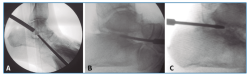

En primer lugar, se aborda la articulación TN como indican Carranza et al.(29); para ello, se marca en la piel el paquete neurovascular dorsal, se chequea la articulación por control fluoroscópico con una aguja intramuscular colocada entre el tendón tibial anterior (TA) y el extensor largo (EHL). Se realiza una incisión solo cutánea de 1 cm sobre la línea articular como el portal artroscópico dorsomedial descrito por Lui(24). Para evitar lesionar la arteria pedia o el nervio peroneal profundo, se realiza disección roma y penetración de la articulación astrágalo-escafoidea lo más cerca posible del TA. Finalmente, se cruenta la articulación bajo control fluoroscópico hasta tejido subcondral con escoplos y brocas motorizadas (Figura 1).

Figura 1. Cruentación de la articulación astrágalo-escafoidea, bajo control fluoroscópico, hasta tejido subcondral, con escoplos (A) y brocas motorizadas (B).